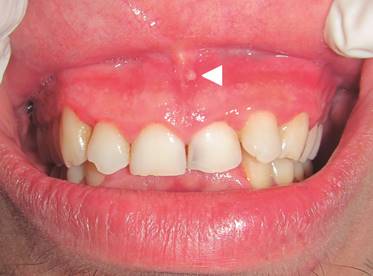

La condición de Fordyce encontrada en el sujeto III.2 se ha asociado alSíndrome de Lynch, y su variante Síndrome de Muir-Torre1.La presencia de tags mucosos se han descrito principalmente en enfermedad de Crohn12; Sin embargo, esta excrecencia mucosa en el frenillo labial encontrada en sujeto III.1, III.2 y III.5 (fig.4), ha sido identificada comoapéndice del frenillo vestibular, un fragmento de tejido mucoso que se desprende desde el frenillo labial del maxilar de herencia autosómica dominante13. Éstos no han sido descritos como manifestaciones orales asociadas a PAF.